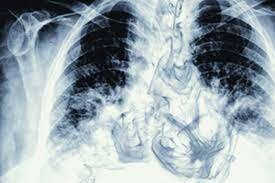

Equipos

EN 2020 Y 2021 el uso de los rayos x para la detención de las enfermedades atraves de los equipos como los razonadores , tomógrafos, y mamógrafos entre otros siempre dejando aun lado siempre los estigmas antiguos